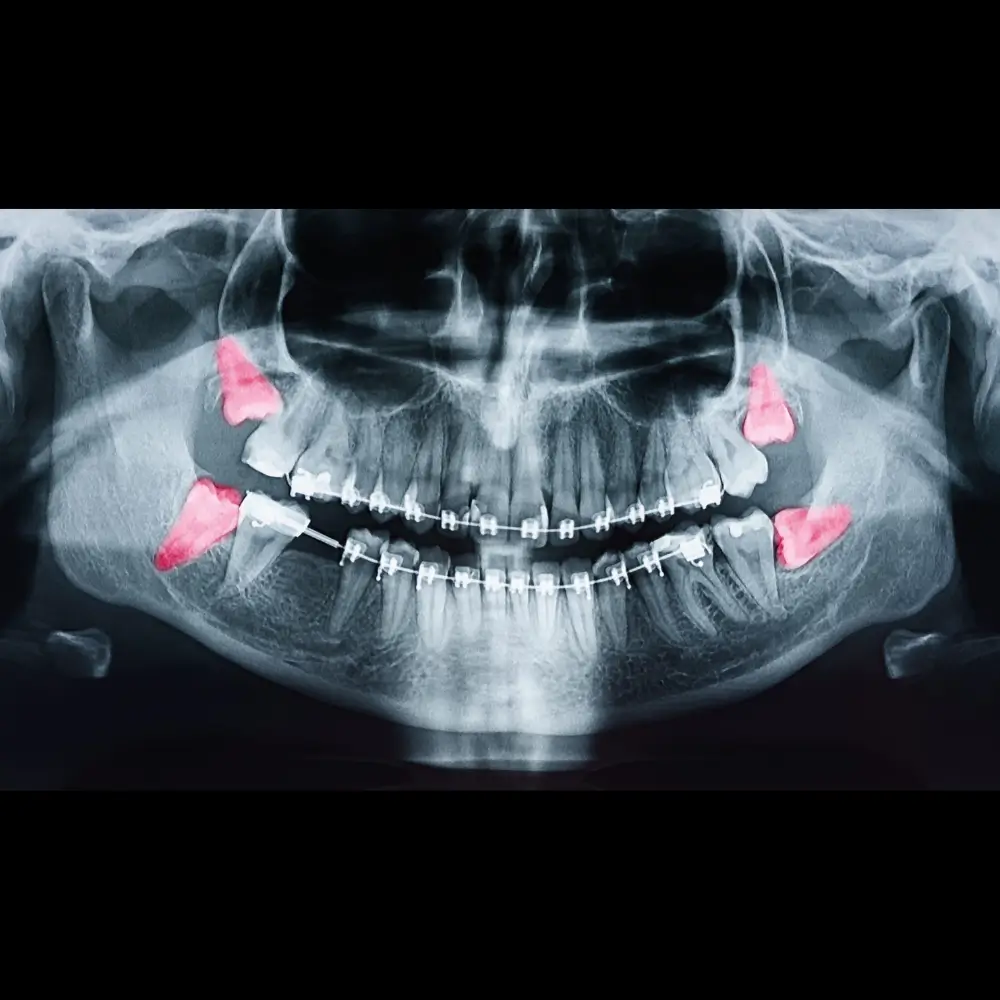

Dents de sagesse, dents incluses, kystes ou apicectomie : nous réalisons vos chirurgies confortablement.

Que ce soit pour une dent de sagesse, une dent incluse, un kyste ou une apicectomie, nous privilégions toujours des gestes doux, une anesthésie confortable et une expérience sereine.

Les dents de sagesse manquent souvent de place pour sortir correctement. Elles s’inclinent, s’infectent, gênent la mastication ou abîment la dent voisine.

Les retirer permet d’éviter la douleur, les inflammations répétées et les complications à long terme.